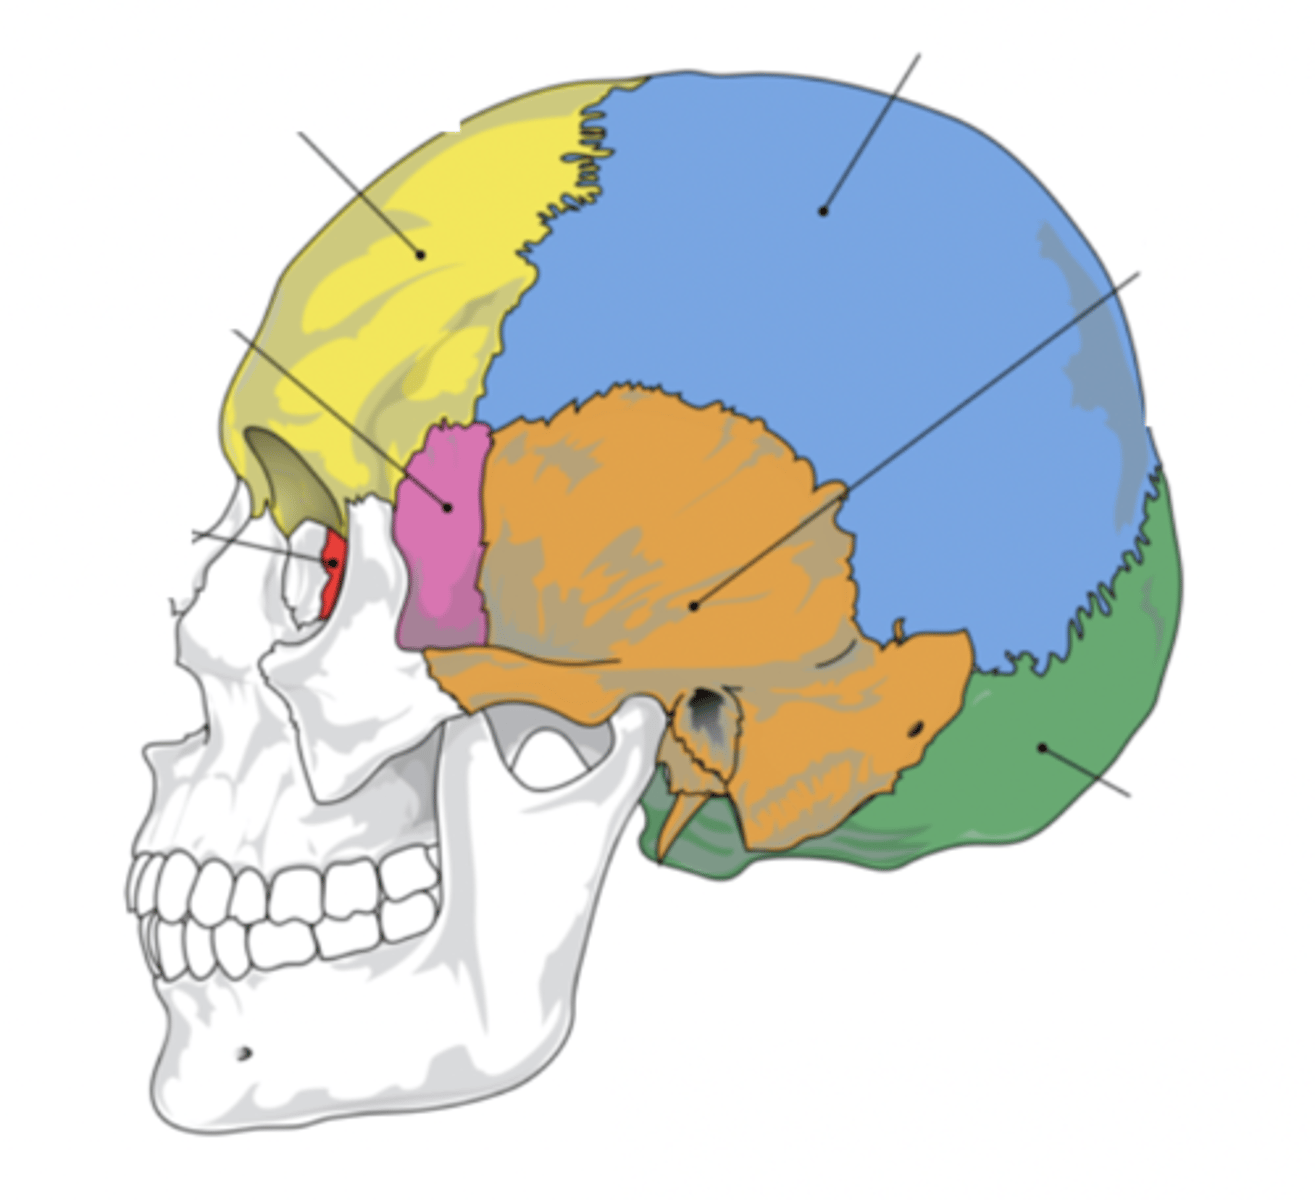

Cranial Bones (8)

- Ethmoid

- Frontal

- Sphenoid

- Temporal (2)

- Occipital

- Parietal (2)

(EFSTOP)

Ethmoid Bone

Forms part of the posterior portion of the nose, the orbit, and the floor of the cranium (red)

Frontal Bone

Bone that forms the forehead (yellow)

Sphenoid Bone

Forms part of the base of the skull and parts of the floor and sides of the orbit (pink)

Temporal Bone (2)

Bone that forms parts of the side of the skull and floor of the cranial activity (orange)

Occipital Bone

Bone that forms the back of the head (green)

Parietal Bone (2)

Either of two skull bones between the frontal and occipital bones and forming the top and sides of the cranium (blue)

4 Main Sutures of the Skull

- Saggital

- Lamboid

- Coronal

- Squamous

(SLCS)

Saggital Suture

Suture that separates the left and right parietal bone

Lamboid Suture

Suture between the occipital and parietal bones

Coronal Suture

Suture between the parietal and frontal bones of the skull

Squamous Suture

Suture between parietal and temporal bones